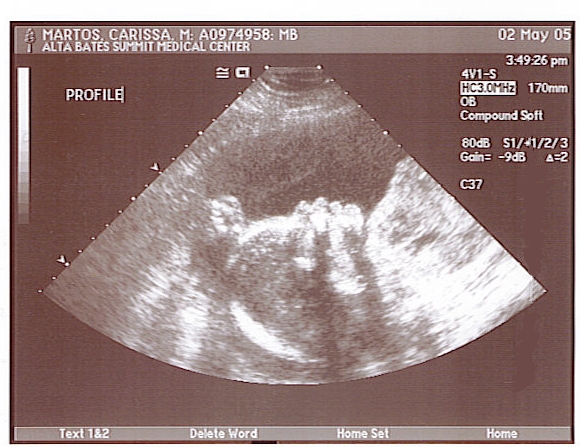

May 2 Update

Another ultrasound today! The tech confirmed that yes, she is a girl. We got two good profile shots (and a great footprint, but the tech didn't print that one). Here's the best profile...